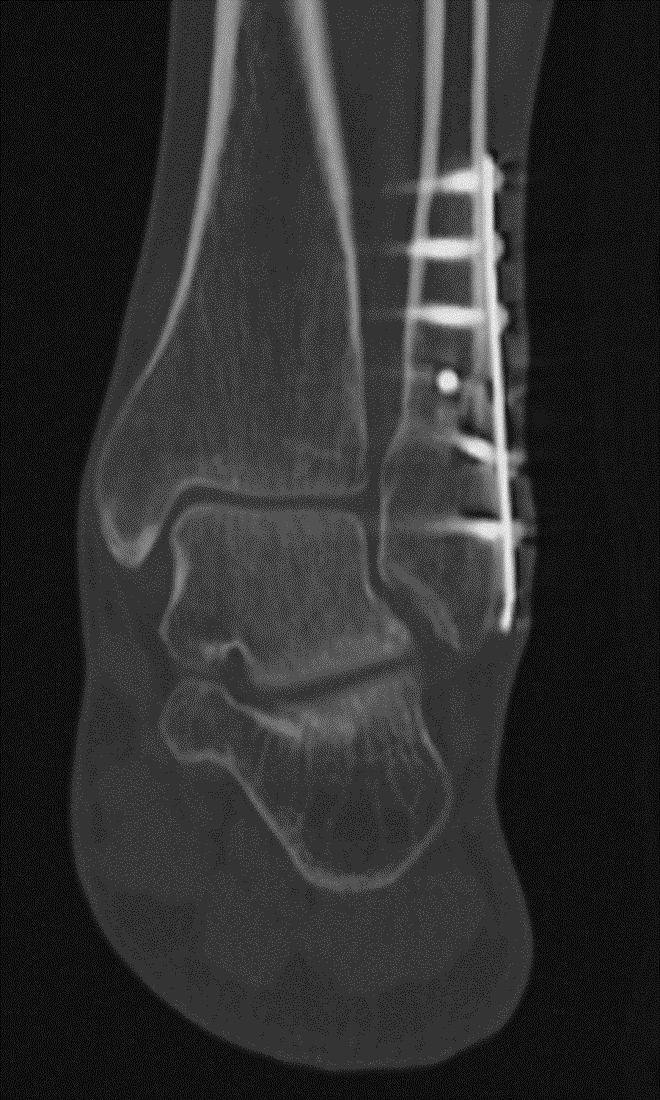

Fracture Union. (A) Sagittal multiplanar reformation demonstrates non-united distal fibular fracture. (B) Follow-up dual-energy CT coronal multiplanar reformation demonstrates distal fibular fracture healing after fixation for non-union.